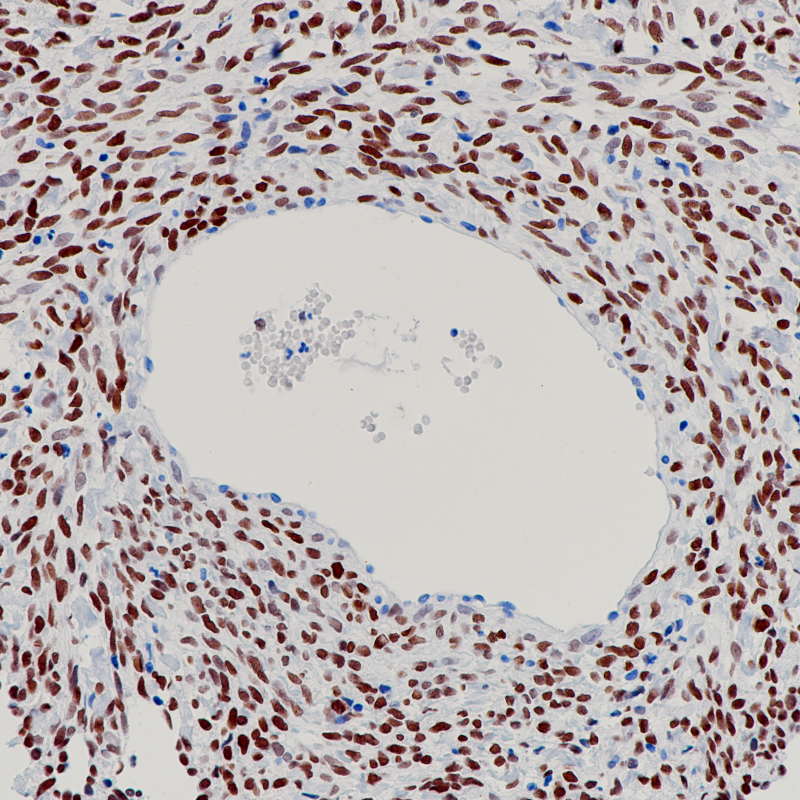

CD5 重组兔单克隆抗体

CD5抗原分布于分布于大多数T 细胞及胸腺细胞(95%)及多数T细胞淋巴瘤。套细胞淋巴瘤和慢性B淋巴细胞白血病和小淋巴细胞淋巴瘤也可阳性,而滤泡性淋巴瘤、毛细胞白血病、大细胞淋巴瘤等为阴性。此抗体有助于对B细胞淋巴瘤进行分类,并且可能有助于区分胸腺癌和肺癌。

阳性对照

阑尾

亚细胞定位

细胞膜